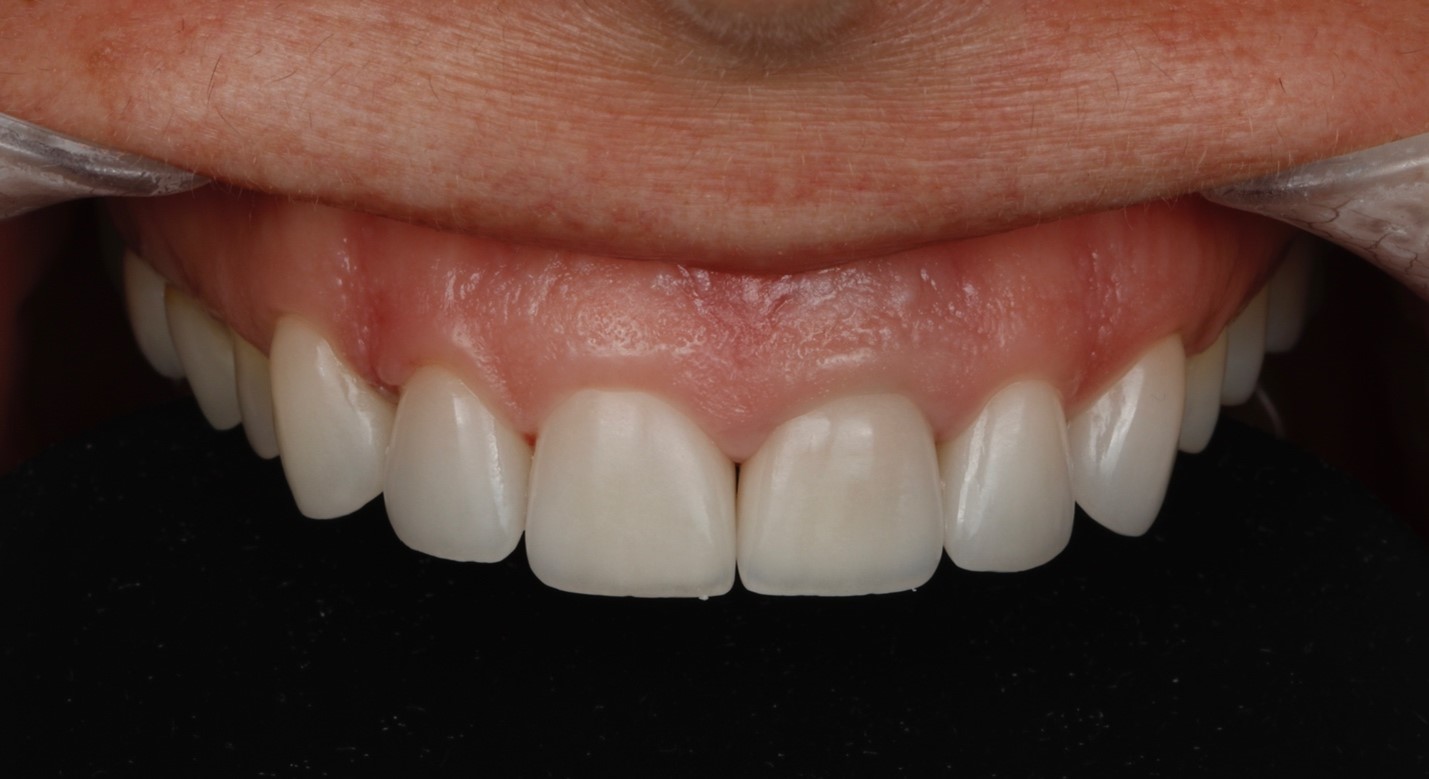

Пациентка И., 43 лет, обратилась в клинику с жалобами на эстетику передних зубов (рис. 1). Зуб 21 ранее проходил эндодонтическое лечение более шести лет назад. На момент первичного осмотра зуб был восстановлен временной композитной коронкой. Зуб 11 имел более тёмный оттенок по сравнению с верхними боковыми резцами. После обсуждения плана лечения пациентка выбрала восстановление зубов с 13 по 23 с использованием керамических реставраций.

Рис. 1. A – вид передней группы зубов с ретракторами. Зуб 21 ранее был пролечен эндодонтически и восстановлен временной коронкой.

B – улыбка пациента.

Через три дня после повторной гидратации зубов пациентка была приглашена на контрольный приём. Отмечено заживление мягких тканей после процедуры фиксации. Также был зафиксирован приемлемый цветовой результат и гармоничное сочетание керамических виниров с окружающими тканями (рисунки 11 и 12). Рентгеновский снимок зуба 21 представлен на рисунке 13.

Рис. 11. Клиническая картина передних зубов верхней челюсти через 3 дня после фиксации.

Рис. 12. Клиническая картина улыбки через 3 дня после фиксации.